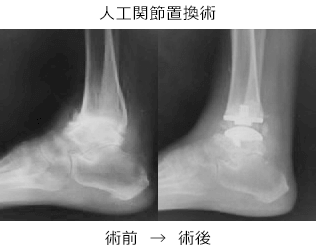

手術療法はそれぞれの部位・変形の程度に応じて、関節温存を目的とした骨切り手術、除痛・変形矯正のための関節固定術、人工関節置換術などが選択されます。

しかし、変形の強い変形性足関節症では、長期にわたり、痛みを確実に取り除くために、手術療法が必要となります。手術療法は関節固定術や関節温存手術、人工関節などがあります。我々は、リング型創外固定を使用した骨切り術による関節温存手術を積極的に行っています。末期の変形性関節症の方に対して関節固定術においても、関節鏡を用いた方法を行うことで侵襲を小さくする方法を行っています。また患者さんの状態に応じて、人工関節手術も行っています。